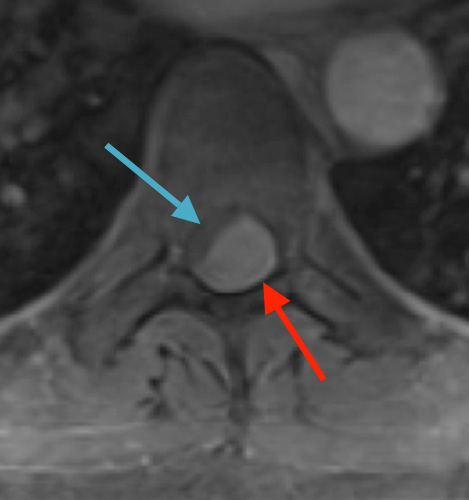

Postoperative MRI T1w demonstrating interval resection with cord re-expansion (blue arrow)

Postoperative MRI T2 illustrating the restoration of CSF surrounding the cord (blue arrow)